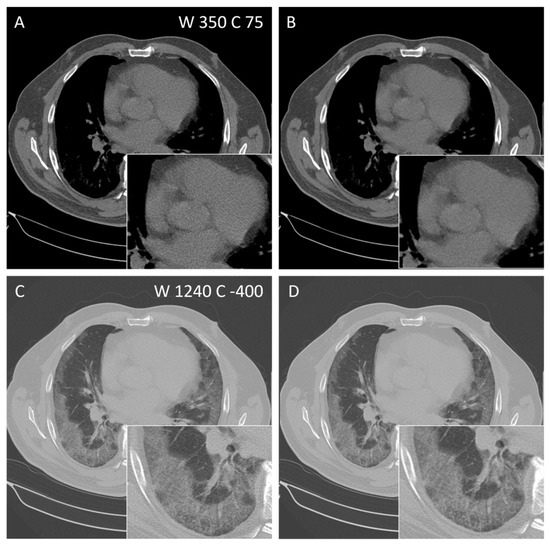

3.4. Subjective Image Quality of Thoracal CT